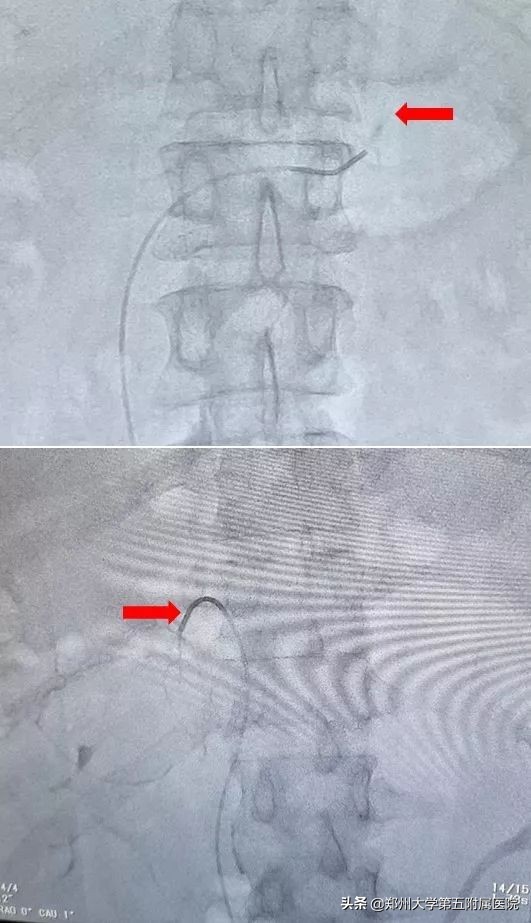

AVS被公认是原醛症分型诊断的“金标准”,是在DSA引导下,将导管插入双侧肾上腺静脉并抽血,通过检测血液醛固酮水平,来确定病患侧,为手术根治高血压提供指导。

▲ 红色箭头分别代表左右肾上腺静脉